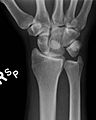

Perilunar dislocation as seen on x-ray.

The lunate bone is the most frequently dislocated carpal bone.